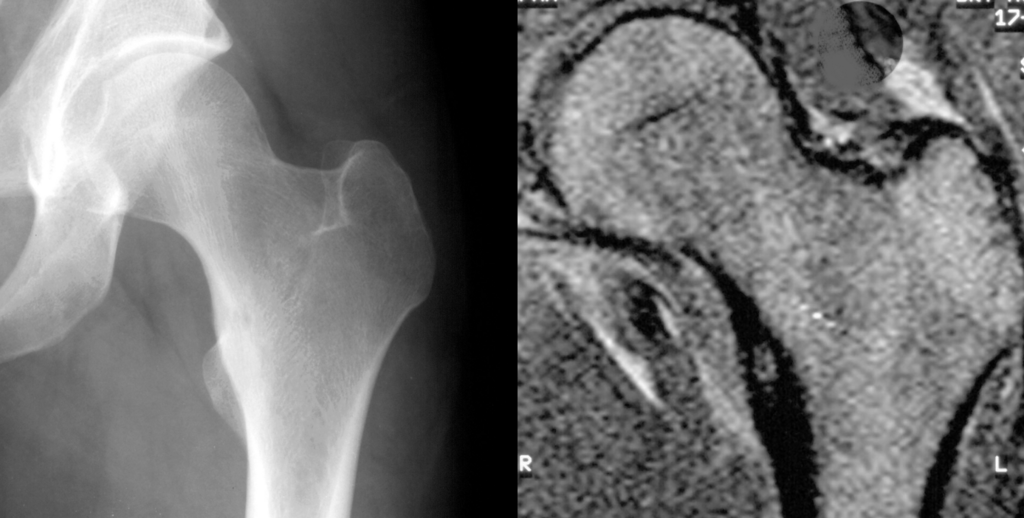

Avascular Necrosis

Avascular necrosis is an ischemic necrosis of bone and bone marrow caused by trauma or fracture.

Risk factors for avascular necrosis include:

- Steroid use

- Sickle cell anemia

- Caisson disease (acute decompression syndrome deep sea divers may experience)

Complications of avascular necrosis include:

- Osteoarthritis

- Fractures